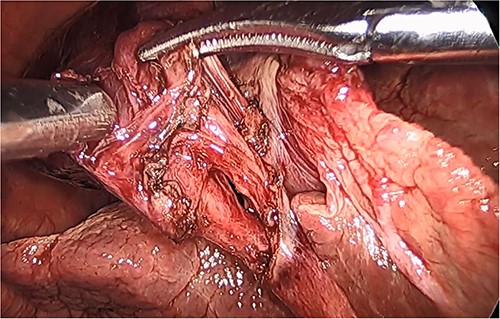

She had a good functional baseline, living in home independently and following anaesthetic review; after a family discussion, the consensus was to proceed to surgery. She underwent a laparoscopic cholecystectomy, and intraoperatively, the diagnosis of gallbladder volvulus was confirmed. A distended gangrenous gallbladder was found, which had undergone 360° clockwise rotation about the cystic duct (Figs 2, 3). The gallbladder was detorted to facilitate a traditional dissection of Calot’s triangle, achieving the critical view of safety (Figs 4, 5). The cystic duct was able to be cannulated facilitating an intraoperative cholangiogram which was unremarkable (Fig. 6). The gallbladder was then removed, and operation was completed without any complications. The histopathology of the gallbladder found diffuse haemorrhagic necrosis of the gallbladder without any evidence of dysplasia or malignancy. No cholelithiasis was present.

Intraoperative picture of the gangrenous gallbladder narrowing upon the torted pedicle; the cystic duct and artery.